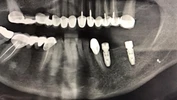

Implant tedavisi

Periimplantitis

Peri-İmplant Mukozitis